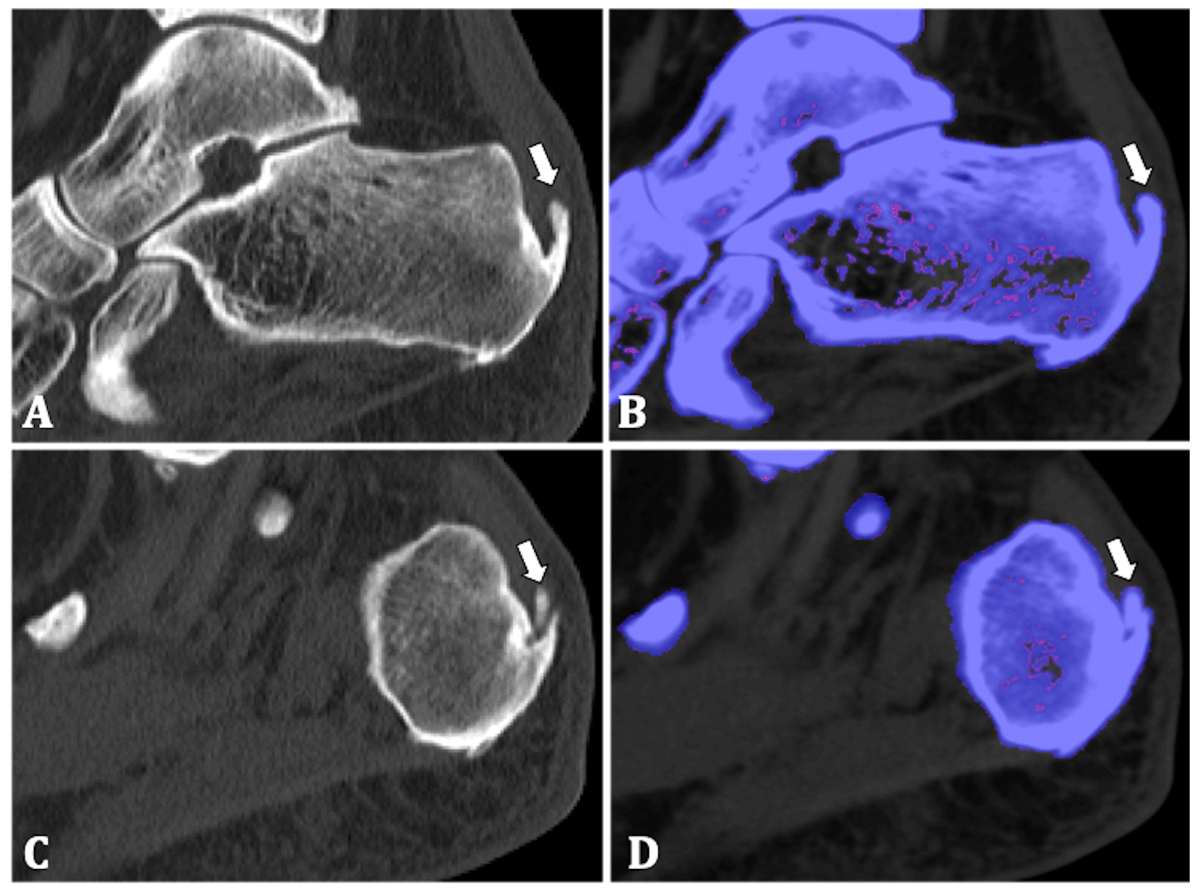

A 70-year-old woman presented with persisting pain in both ankles and the left Achilles tendon for two years. Recently the pain also started in her right Achilles tendon and the MTP-I on the left. She had pressure pain in both ankles, a painful swelling of the right Achilles tendon and 4.7 mg/dL uric acid in the blood. DECT was performed to help differentiate between gout and calcific tendinopathy. The same DECT setup as in the previous cases was used.

DECT showed enthesophytes at the insertion of the left and right Achilles tendon and bilateral calcaneal spur, most dominantly on the left. No erosions or MSU depositions were found (Figure 3). These findings suggested a mechanical etiology of the patient’s articular pain and gout was excluded.

Figure 3

70-year-old woman. (A, C) Sagittal native CT image of the left and right calcaneum respectively show enthesophytes at the Achilles tendon insertions (arrows). (B, D) Post-processing shows there is no uric acid deposition (arrows).